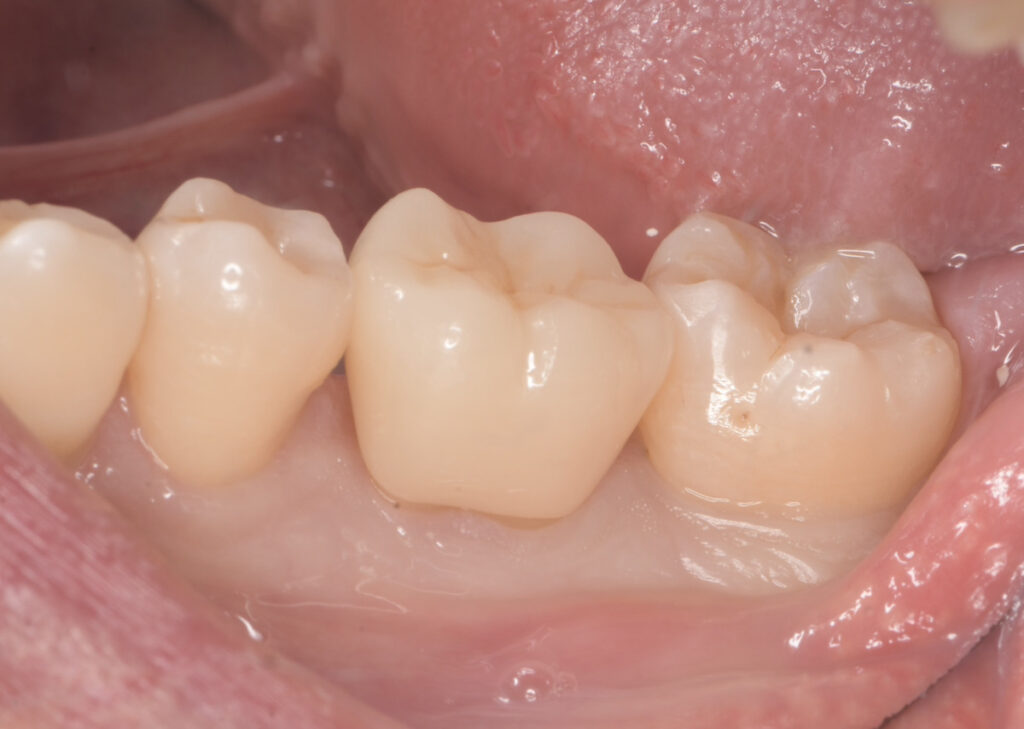

30代 男性

「左下の奥歯が、冷たいもの・温かいもので激しく痛む」

レントゲンおよび口腔内の確認により、

神経まで達した重度の虫歯(C3)を認めました。

その後ラバーダム防湿を行い、インレーと呼ばれる金属を除去。

虫歯を取り除いていくと、根の深い部分からの出血が止まらず

神経を取る処置(抜髄)となりました。

その際に歯に細かなヒビ(クラック)が確認されました。

歯のヒビは、日常的な食いしばりや歯ぎしり、硬いものを噛んだ際の負担などによって

生じることがあります。見た目では分かりにくく、

気づかないうちに進行してしまうことも少なくありません。

この患者様の場合も、ヒビから細菌が侵入し、内部で虫歯が進行していました。

その結果歯の神経まで感染が及び、神経の治療が必要な状態となっていました。

この後、最終的な被せ物(今回はジルコニアクラウン)を被せて治療は終了です。